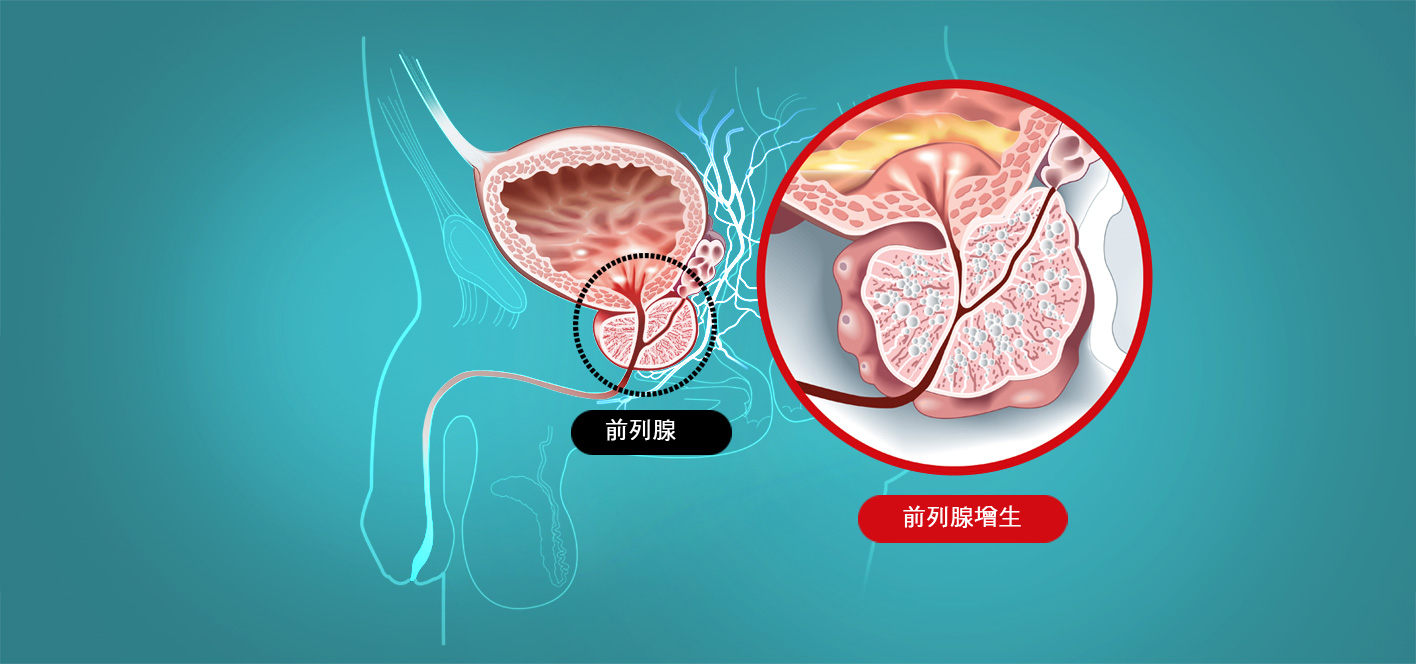

前列腺是男性独有的生殖器官,位于膀胱下方和直肠前方。它覆盖尿道,即尿液通道,并产生约 30% 的精液。如果前列腺肿大,就会压迫尿道,导致多种泌尿系统疾病。

前列腺是男性独有的生殖器官,位于膀胱下方和直肠前方。它覆盖尿道,即尿液通道,并产生约 30% 的精液。如果前列腺肿大,就会压迫尿道,导致多种泌尿系统疾病。